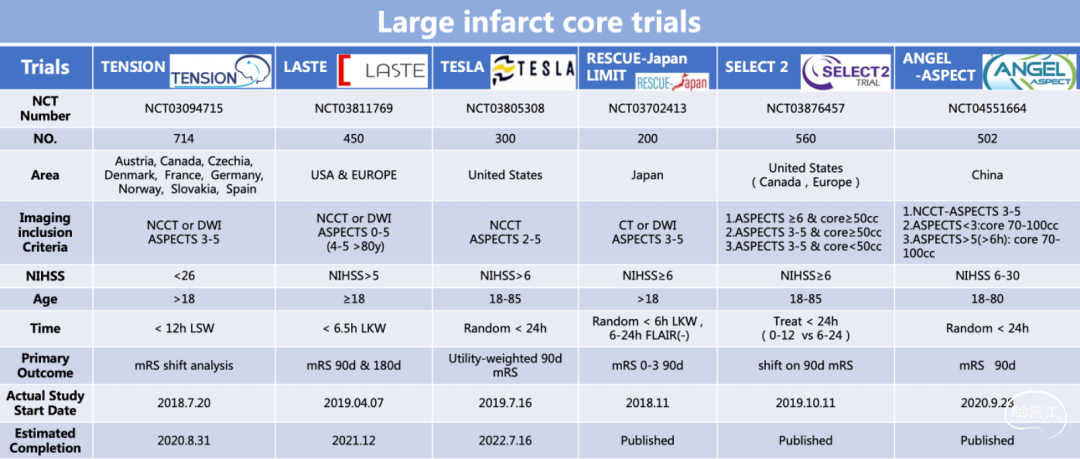

ANGEL-ASPECT研究的出发点主要人群是临床应用最广泛的CT-ASPECTS评分评估下3-5分的患者,这部分患者虽然在指南中并没有最高级别推荐取栓,但潜在获益的可能性极大,开展临床研究具有可行性,对于适应证的拓展大有裨益。目前,国际上有六项研究在进行大核心梗死取栓的探索,每个研究的入排标,研究人群准都各有差异。目前,三项研究(RESCUE Japan LIMIT,ANGEL-ASPECT,SELECT2)发表在NEJM上,TESLA已经完成入组,TENSION研究在进行中期分型。相信这些研究的结果会对指南产生深远的影响。